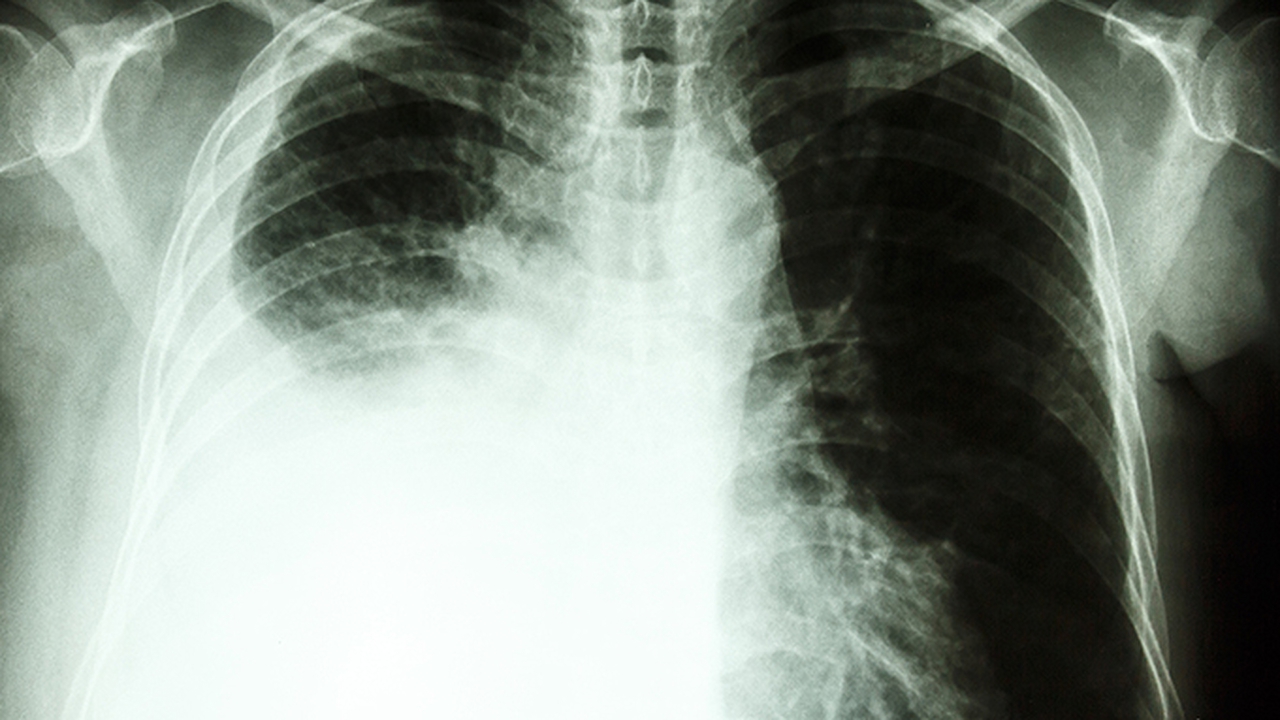

肺部疾病种类繁多,包括肺炎、慢性阻塞性肺病、哮喘、肺结核等,发病原因涉及感染、环境污染、遗传因素等。及时就医对控制病情发展至关重要。